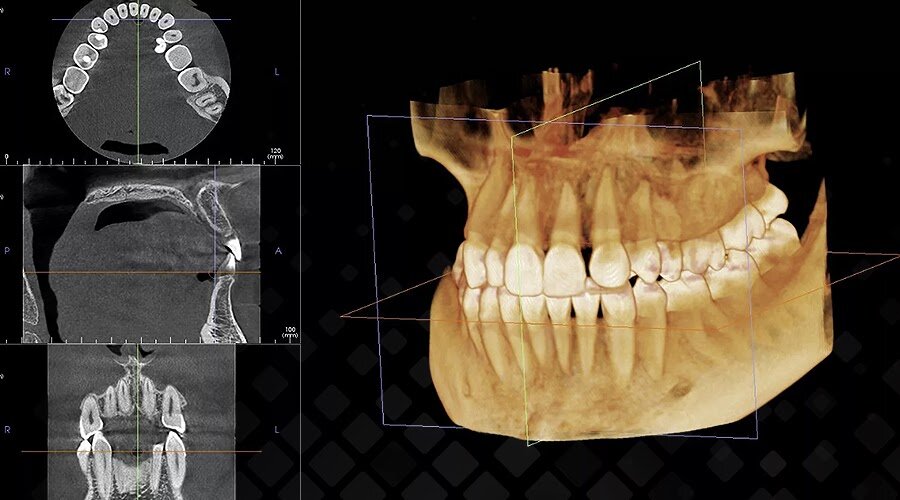

Компьютерная томография (КТ) челюстно-лицевой области

- Что это? Трехмерное (3D) изображение, которое создается путем послойного сканирования.

- Что показывает? Врач видит не просто картинку, а точную объемную модель всей вашей челюсти и может изучать ее с любого ракурса, в любом «срезе».

На 3D-модели хирург может точно измерить расстояние до этих структур с точностью до миллиметра.